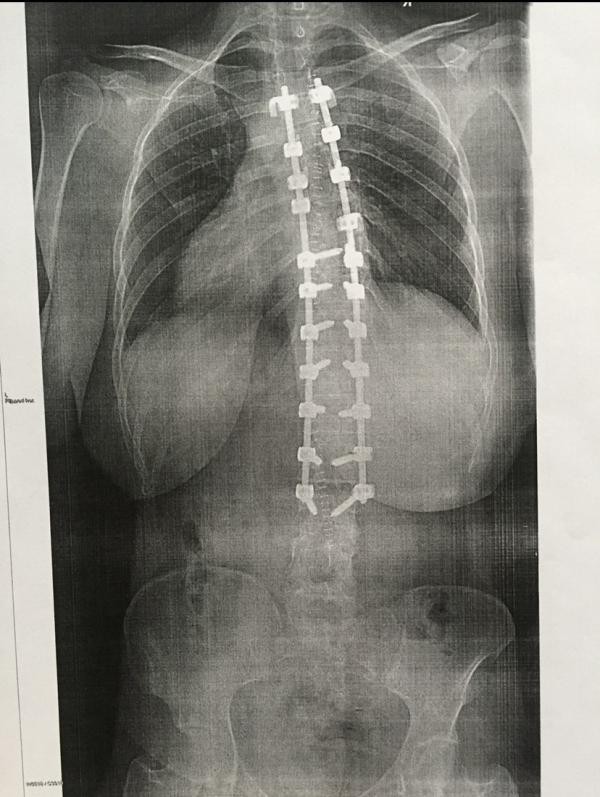

Ну и по по традиции, так как вы моя Прегги семья) и почти все обо мне знаете🙈 делюсь с вами личными моментами) сегодня ровно 4 года со дня операции) я до сих пор этот день воспринимаю как праздник, как важную дату) это все действительно разделило мою жизнь на до и после) в лучшем понимании этих слов) несмотря на то что я так и осталась кривенькая и косенькая, несмотря на огромный шрам(который я очень люблю), я себя чувствую в миллион раз увереннее, чем раньше) потому что, во-первых, я просто соб...